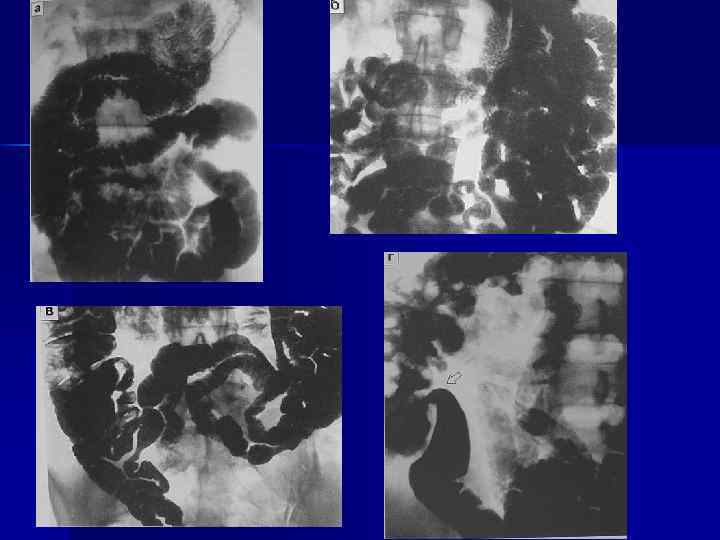

Нормальная тонкая кишка 28

При пероральном контрастировании рельеф внутренней поверхности имеет перистый рисунок из-за вторичных складок слизистой, которые при интубационной энтерографии разглаживаются

Поступление бариевой взвеси в слепую кишку начинается через 3 -4 -5 часов после ее приема и осуществляется ритмично отдельными порциями Эвакуация из тонкой кишки в толстую длится 7 -9 часов

Нормальная рентгенанатомия тощей кишки.

При энтероклизме, когда происходит оптимальное растяжение, толщина поперечных складок доходит до 2 мм, они выглядят подобно лесенке и располагаются циркулярно по всей ширине просвета